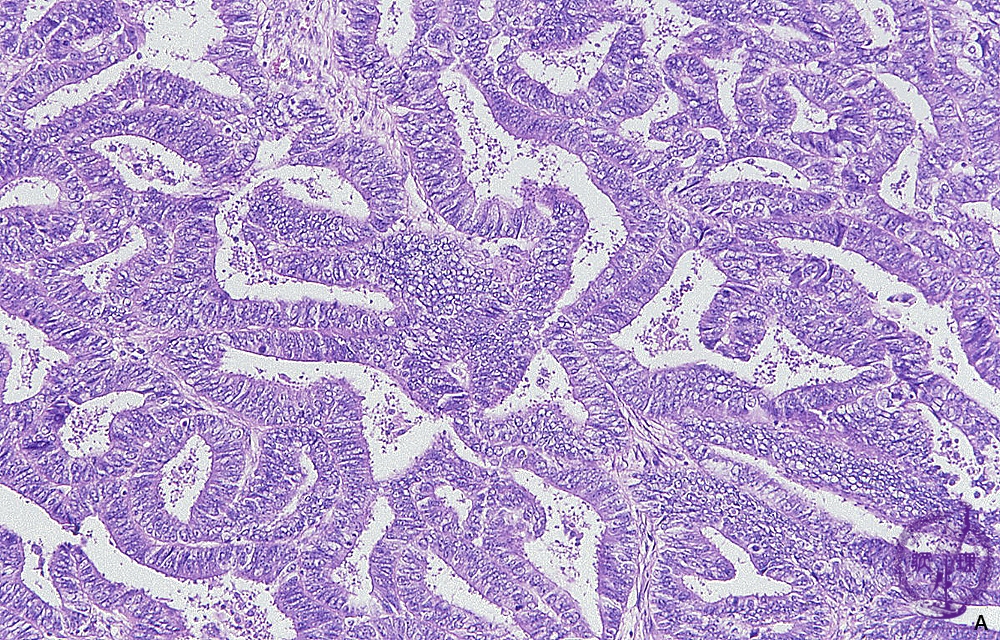

Histology (HE stain, intermediate power): Endometrioid adenocarcinoma of uterine corpus. The most common tissue type. Carcinoma cells mimick the proliferative endometrium.